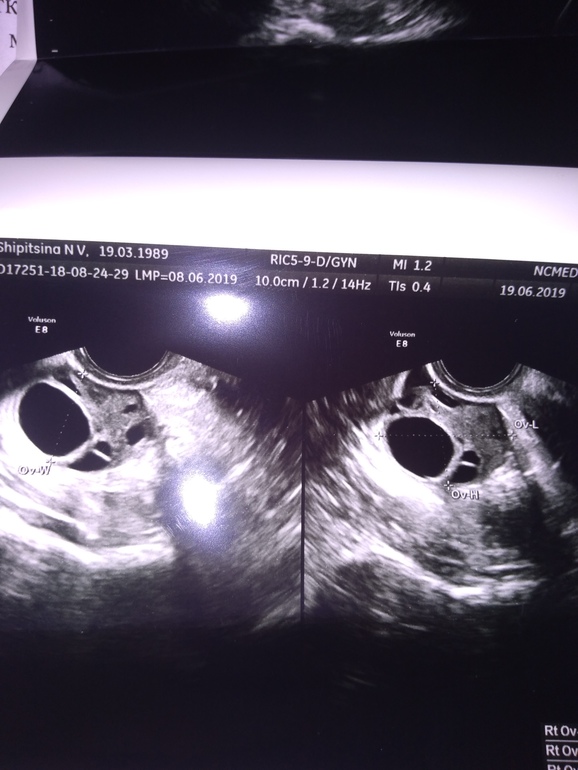

Узи на 12 дц. Стимуляция клостилбегит

Сегодня На Узи эндометрий 8,8 мм. В ПЯ округлое анэхогенное образование с четкими контурами с утолщенной капсулой, при ЦДК локусы кровотока. Диаметр 24 мм. Узистка говорит либо ДФ либо ЖТ, точно не понятно. Жидкости за маткой нет.